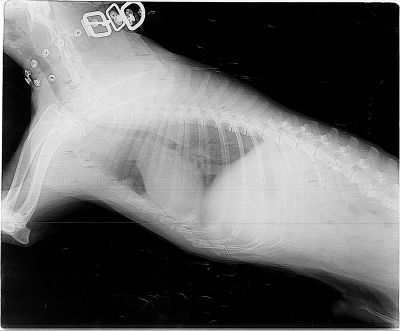

Коллапс трахеи форум